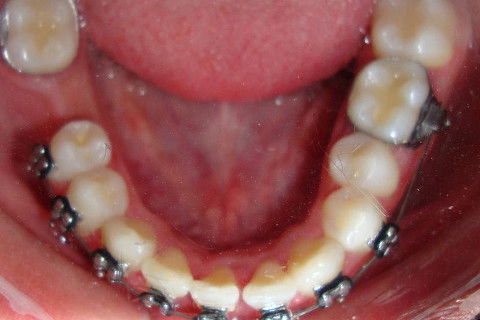

Exodontia Incisivo Inferior

Paciente D. F. S., 19 anos, com queixa principal o apinhamento superior e inferior. Realizado o diagnóstico foi proposto duas opções de tratamento: exodontia de 04 pré-molares ou exodontia de incisivo inferior e slices superior, verticalização do molar 47 para futura instalação de implante do 46.

O paciente optou pela segunda opção, estando de acordo com as vantajens e desvantagens da terapia.

O tratameno foi iniciado com a montagem completa do aparelho superior e inferior, a indicação da exodontia do elemento 41, alinhamento e nivelamento.

Atualmente estamos com  04 meses de tratamento, podemos notar uma grande evolução no caso em pouco tempo.